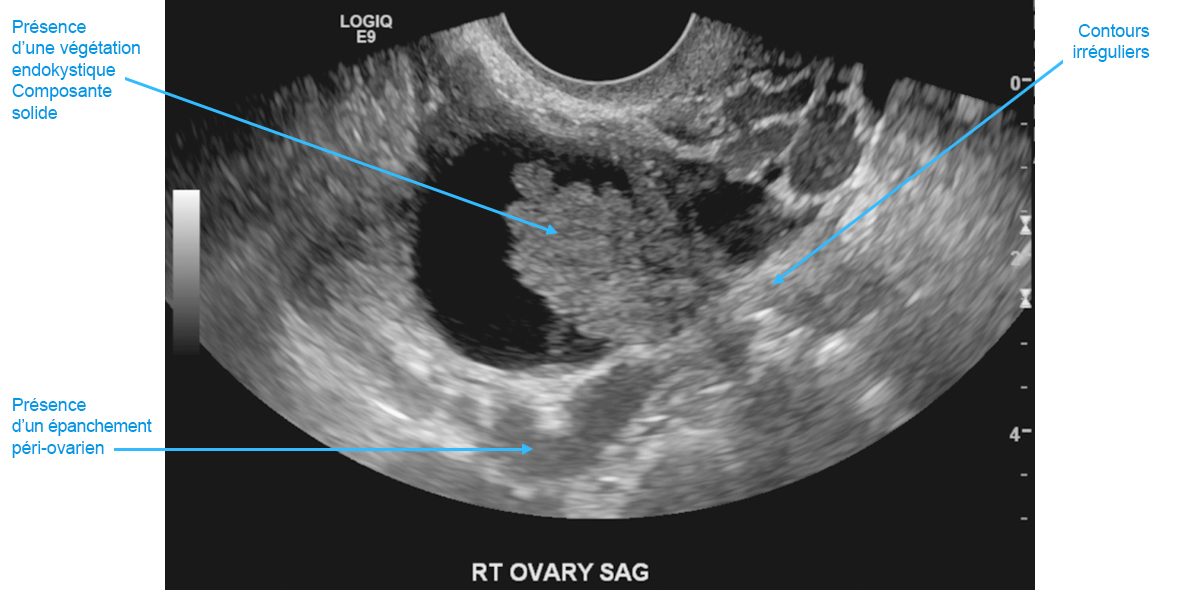

Le scanner abdominal retrouve une ascite importante associée à des nodules de carcinose péritonéale diffus et une masse pelvienne. Il n’existe pas de niveau jonctionnel sur le scanner mais un iléus reflexe important. Vous réalisez une échographie pelvienne qui retrouve cette image semblant être d’origine annexielle. Source : S. Khiat.

Question 12 - Quels critères échographiques en faveur d’une origine organique relevez-vous ?

Il convient de différencier les lésions ovariennes selon différents critères afin d’orienter vers une origine fonctionnelle (évolution kystique d’un follicule mature) ou organique (développé aux dépens d’un certain type cellulaire constituant le stroma ovarien).

En 2008, les auteurs du groupe IOTA (International Ovarian Tumor Analysis) ont publié des « règles simples » de l’évaluation endovaginale du kyste ovarien.

Cinq critères en faveur de la « malignité » : – tumeur solide irrégulière ; – présence d’un épanchement péritonéal ; – présence d’au moins quatre végétations ; – tumeur irrégulière multi-cloisonnée solide dont un des diamètres est supérieur à 10 cm ; – score colorimétrique fort en Doppler couleur.

Cinq critères en faveur de la « bénignité » : – kyste uniloculaire ; – présence de composantes solides dont le plus grand diamètre est inférieur à 7 mm ; – cône d’ombre ; – masse multiloculaire lisse avec un diamètre maximal inférieur à 100 mm ; – absence de flux en Doppler couleur. Source : S. Khiat.